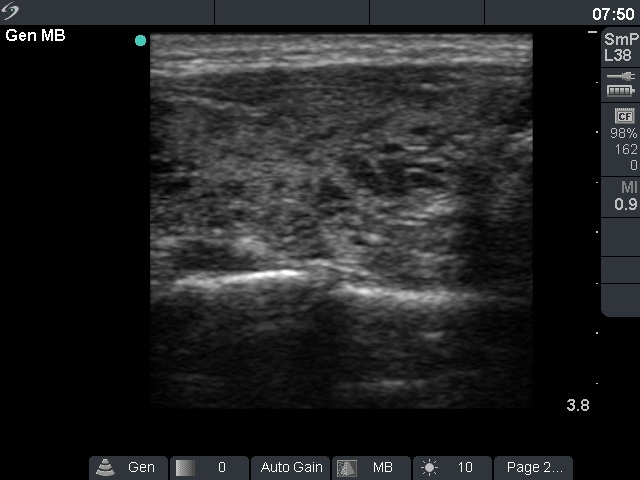

Ultrasonography: there were multiple small hypoechogenic areas in both lobes. The borders of these lesions were irregular. The US pattern corresponded to autoimmune thyroiditis.

Comment: the greatest issue in thyroid ultrasonography is the misinterpretation of hypoechogenic areas of Hashimoto's thyroiditis as nodules. Although the US pattern was unequivocal, we performed FNAC mainly for a psychological reasons. The term 'nodule' caused great fear of cancer. In this case, there was a second reason of aspiration: the negative anti-TPO test.